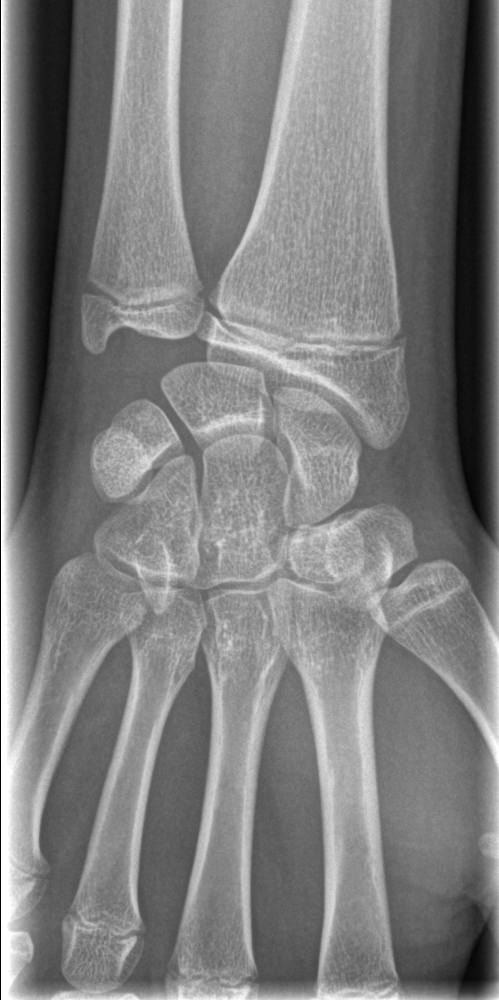

白色文字(排除指定关键词) Imaging Anatomy: interactive PACS-like atlas of radiological anatomy

解剖学模块